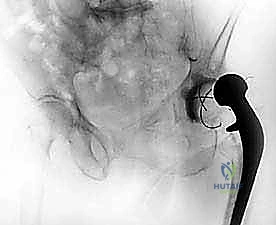

- الاستخراج المعقد (Implant Removal): يتم فتح المفصل بحذر شديد لحماية الأنسجة المتبقية. يقوم الدكتور هطيف باستخدام أدوات جراحية دقيقة ومتخصصة لإزالة المفصل الصناعي القديم (الساق المعدنية، الكوب الحُقي، والمسامير). التحدي هنا هو إزالة هذه الأجزاء دون التسبب في كسور إضافية للعظم الذي قد يكون هشاً بسبب العدوى.

- تشكيل ووضع المباعد الأسمنتي (Antibiotic-Loaded Cement Spacer): بعد التأكد من نظافة الحقل الجراحي، يقوم الجراح بخلط "أسمنت عظمي" طبي مع جرعات عالية جداً من المضادات الحيوية (يتم اختيارها بناءً على المزرعة البكتيرية السابقة).

- يتم تشكيل هذا الأسمنت ليأخذ شكل مفصل الورك المؤقت.

- وظيفة المباعد: يحافظ على طول الساق، يمنع انكماش العضلات المحيطة بالورك، والأهم من ذلك: يقوم بإفراز تركيزات عالية جداً من المضادات الحيوية مباشرة في مكان العدوى على مدار الساعة، وهو ما لا يمكن تحقيقه بالأدوية الفموية.

بعد نجاح المرحلة الأولى، تبدأ فترة حرجة تتراوح عادة بين 6 إلى 12 أسبوعاً. في هذه الفترة، يعيش المريض بالمفصل المؤقت (المباعد).

- الحركة المحدودة: يُسمح للمريض بالمشي باستخدام مشاية أو عكازين، مع تقييد الوزن المسموح بوضعه على الساق المصابة حسب تعليمات الجراح.

ثالثاً: المرحلة الجراحية الثانية (إعادة الزرع النهائي)

بمجرد التأكد من خلو الجسم من العدوى، يعود المريض لغرفة العمليات لإجراء الجراحة النهائية.

- إزالة المباعد: يتم فتح الجرح القديم وإزالة المباعد الأسمنتي بحذر.

- زراعة مفصل المراجعة المعقد (Revision Arthroplasty): المفاصل المستخدمة في هذه المرحلة تختلف عن المفاصل الأولية؛ فهي مصممة لتكون أطول، وأكثر استقراراً، وتحتوي على آليات تثبيت معقدة لتعويض ضعف العضلات والأربطة. يتم تثبيت الكوب الحُقي الجديد وساق الفخذ بدقة ميكانيكية حيوية فائقة لضمان عدم تعرض المريض للخلع مستقبلاً.